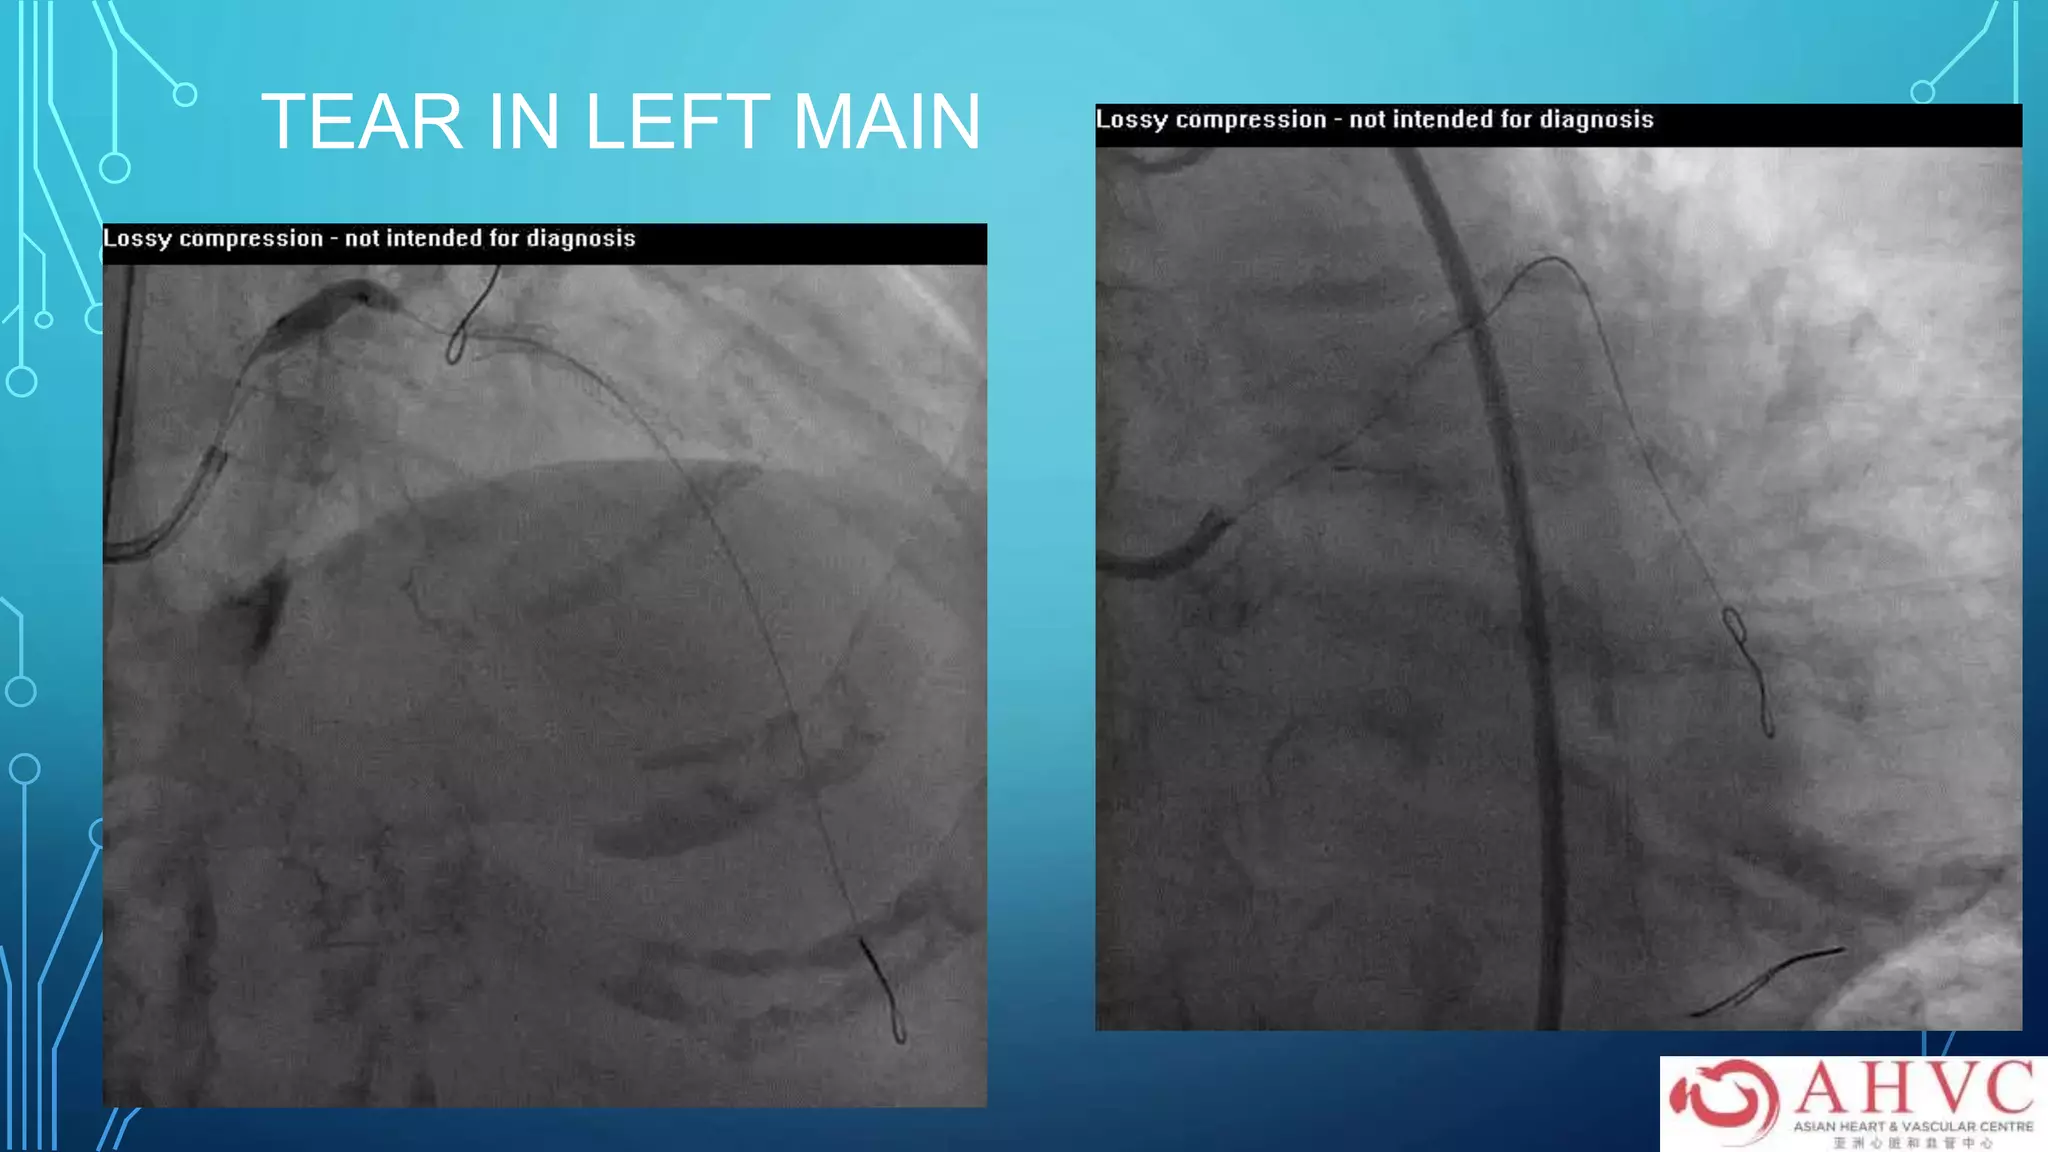

TEAR IN LEFT MAIN

PROTECT LCX WITH

STENT

ROTABLATE LM THEN STENT

FINALLY